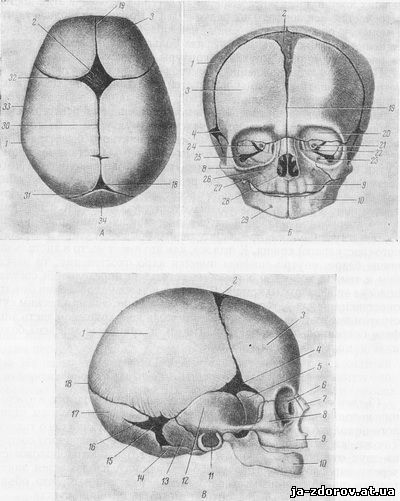

Анатомия детского черепа: Рентгеновские снимки и описание